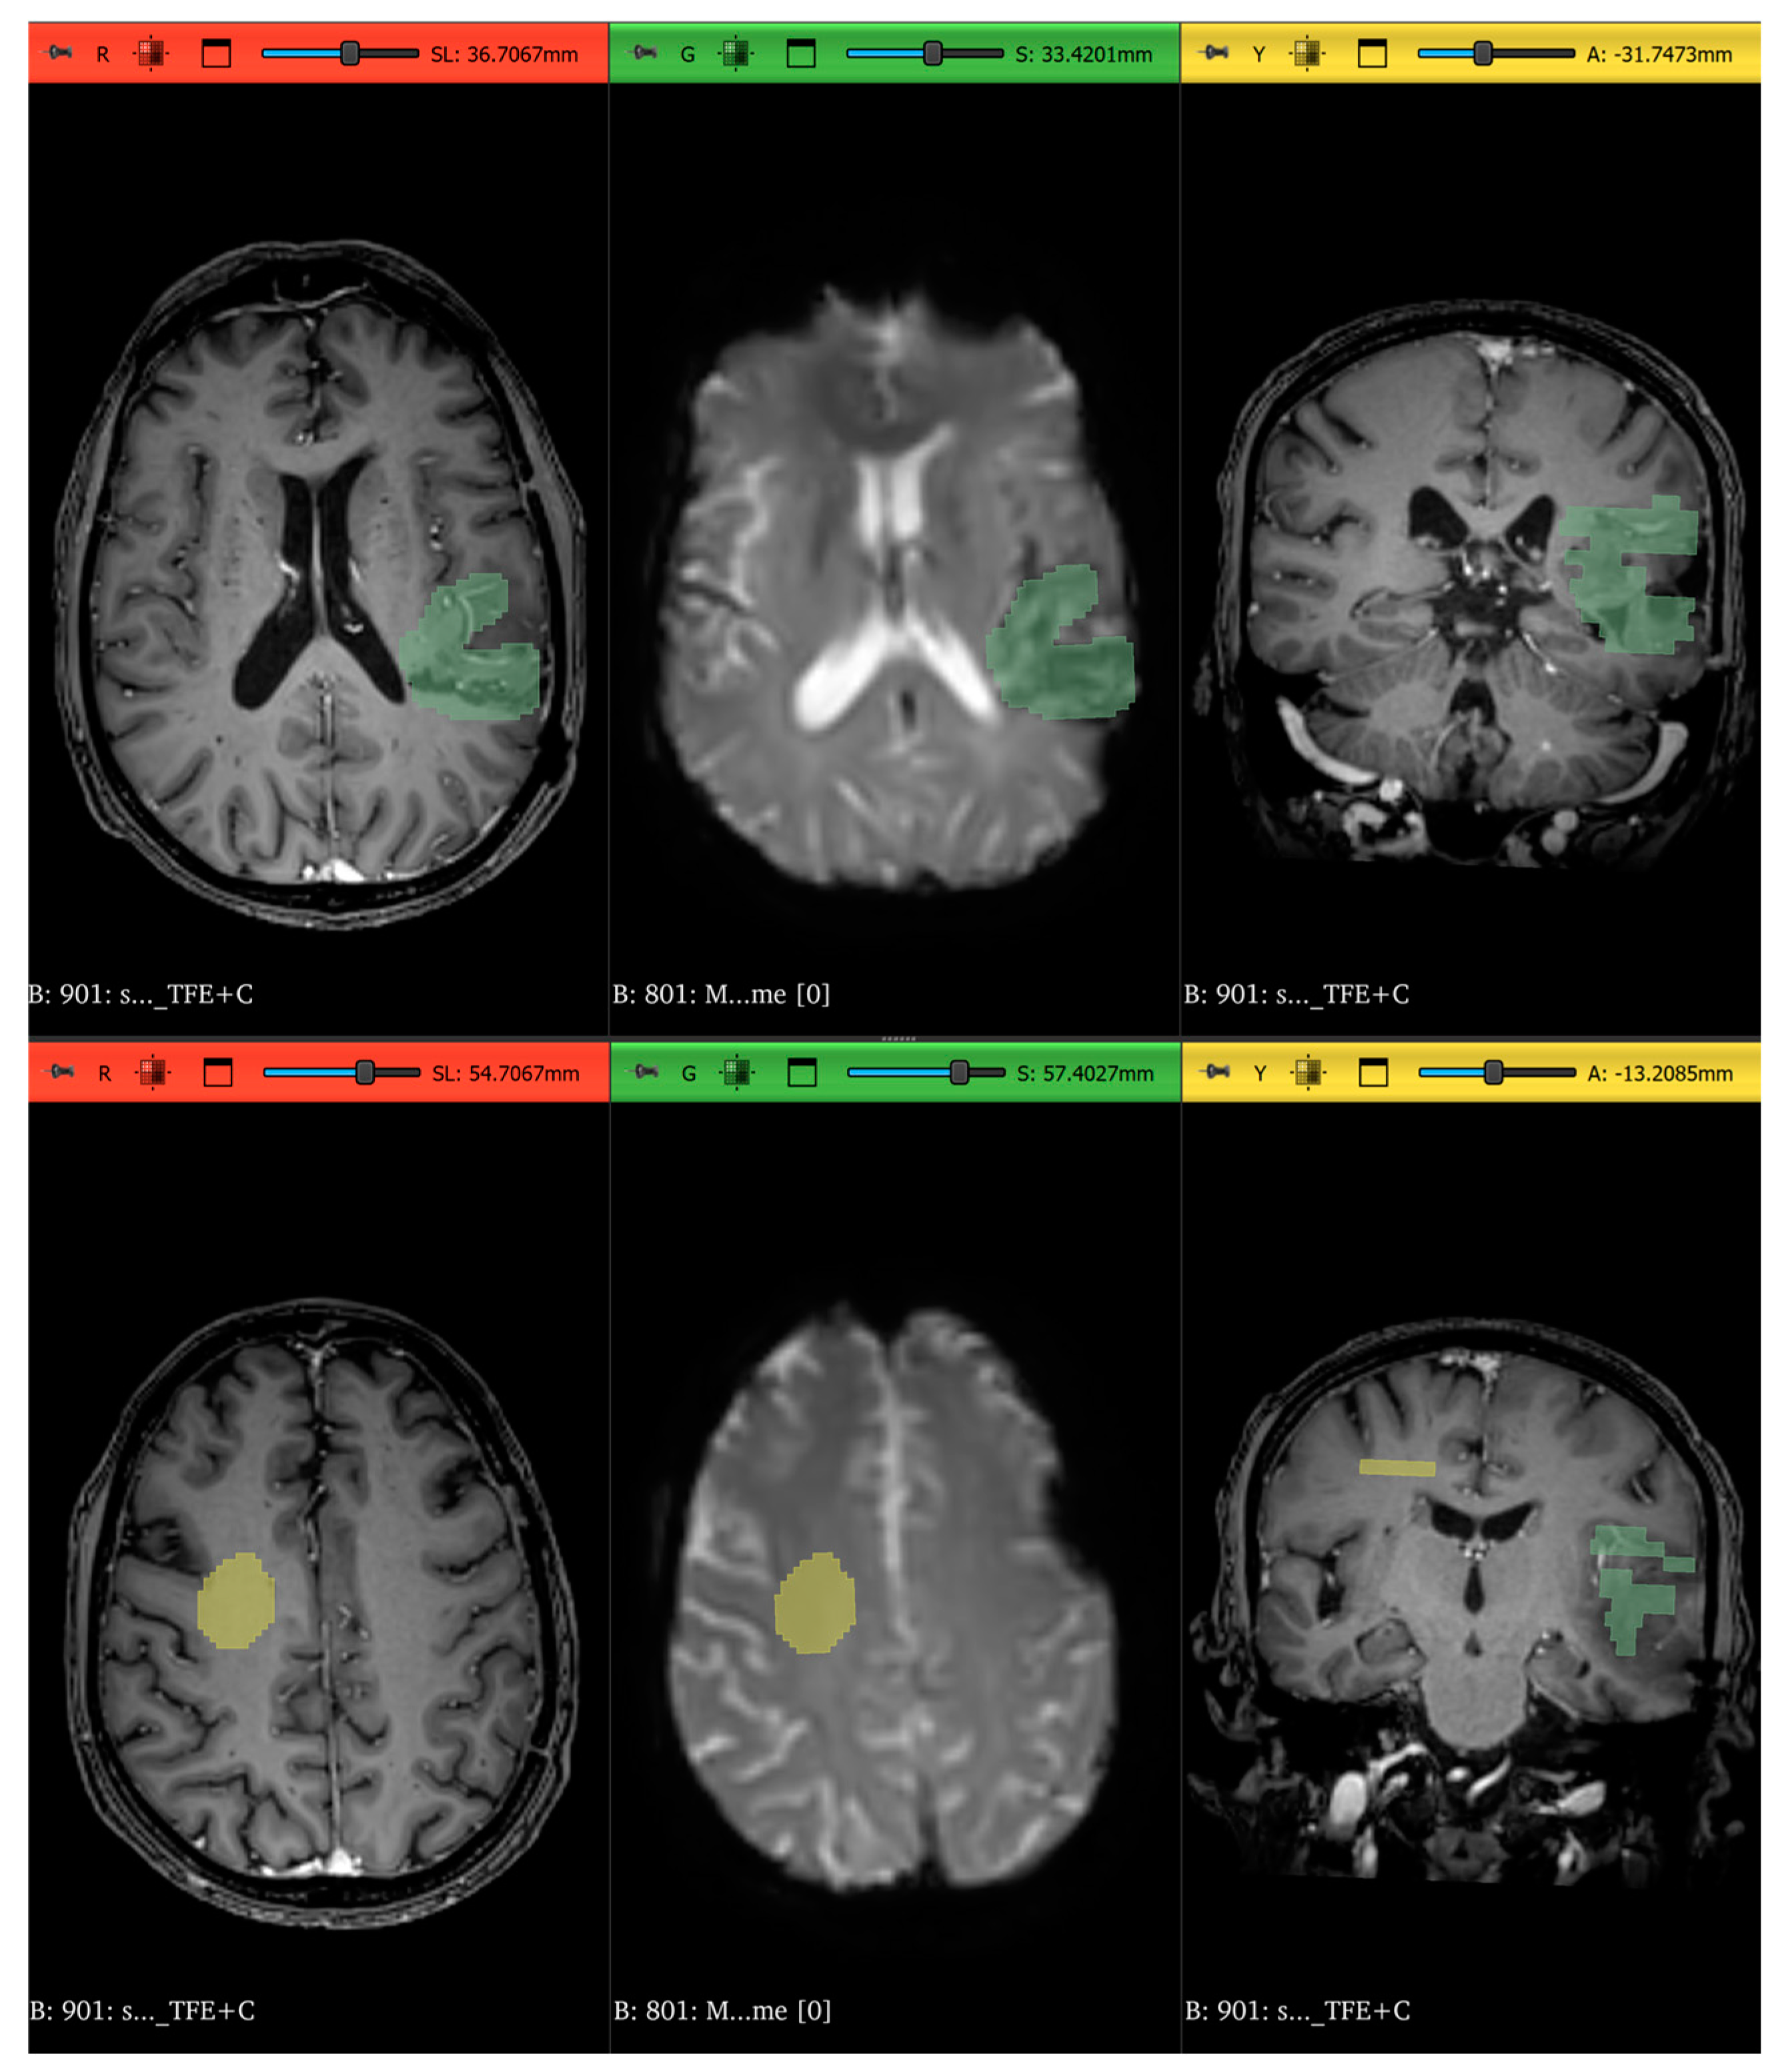

2.3. Radiomics Features Extraction